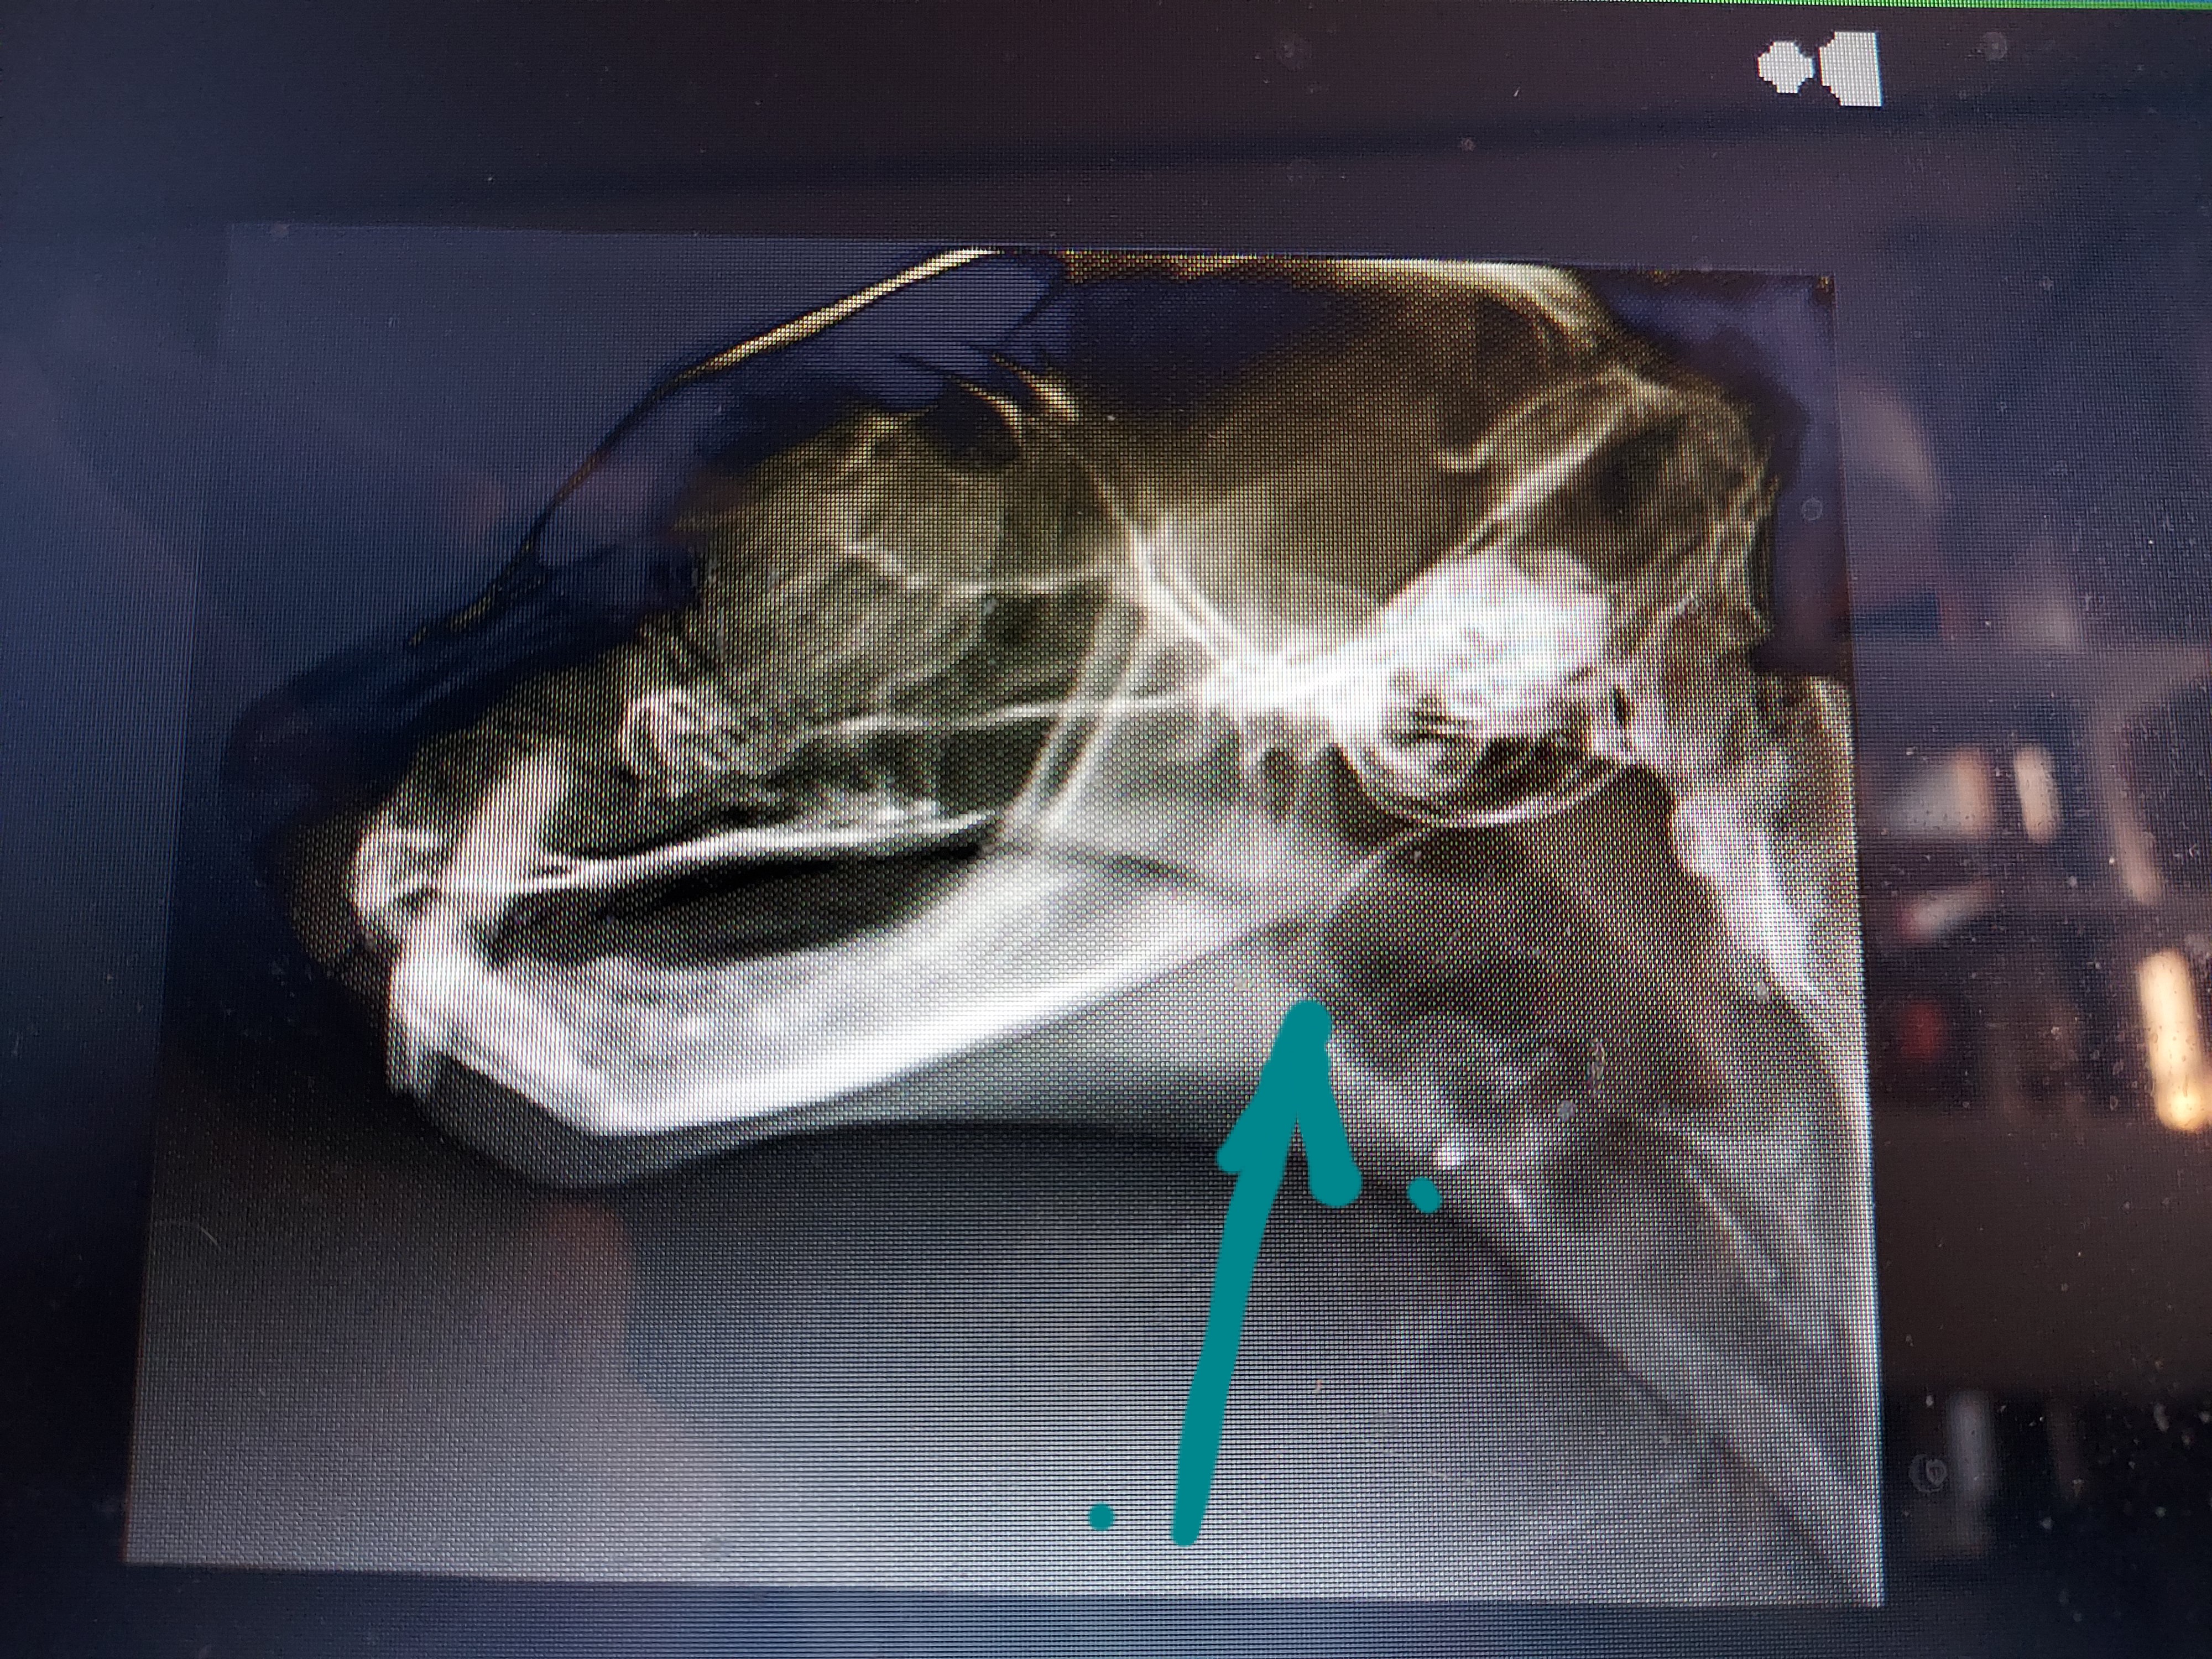

この矢印の白い線が膜です。

レントゲン写真からこの白い線変だよね?ってことで内視鏡をして